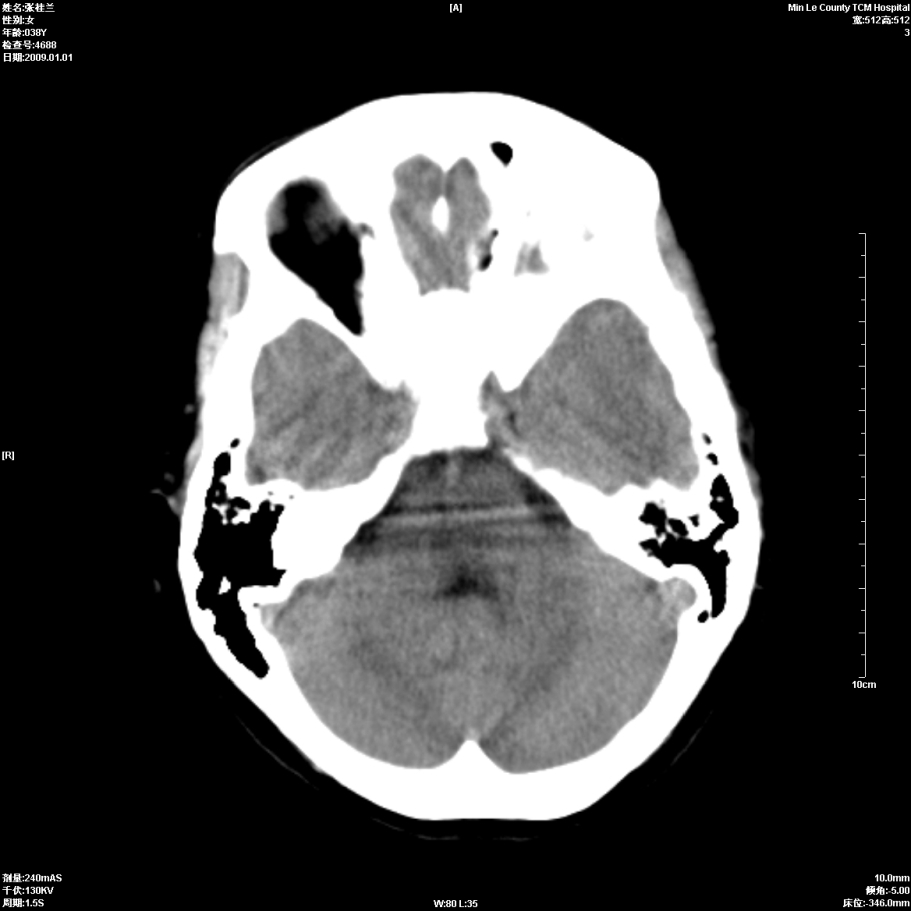

以下是引用hhcckk在2009-1-1 15:56:00的发言:[br]癫痫的原因一般与四种因素有关:[br] 1.遗传因素在一些有癫痫病史或有先天性中枢神经系统或心脏畸形的病人家族中容易出现癫痫;[br] 2.脑损害与脑损伤在胚胎发育中受到病毒感染放射线照射或其它原因引起的胚胎发育不良可以引起癫痫;胎儿生产过程中产伤也是引起癫痫的一个主要原因;颅脑外伤也可引起癫痫;[br] 3.颅脑其它疾病脑肿瘤脑血管病颅内感染等;[br] 4.环境因素;男性病人较女性病人稍多农村发病率高于城市另外发热精神刺激等也是癫痫发生的诱因。[br][br]此病例在额叶有片状低密度灶,无明显占位与负占位效应,结合癫痫的常见原因考虑[br]1、外伤后软化灶,包括产伤,可以结合病史鉴别[br]2、血管畸形的窃血现象形成的萎缩?

以下是引用xulianj在2009-1-1 16:09:00的发言:[br]支持:蛛网膜粒囊肿!